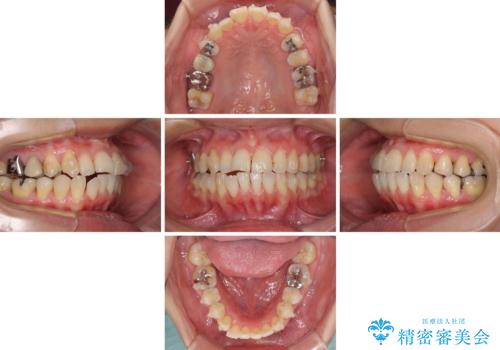

切端咬合をインビザライン矯正で解消

- 前歯のデコボコを気にして来院された患者様です。

上下前歯の先端同士が接触する切端咬合であったため、上顎は歯列を拡大し、下顎はIPR(歯と歯の間を削る)により叢生を解消しながら歯列を小さくすることとしました。

矯正装置にはインビザラインを用いることとしました。

治療途中に前歯に歯髄充血を思わせる痛みが認められたため、無理のない歯の移動と頻繁な経過観察を行いました。

切端咬合はスムーズに解消され、前歯の負担を軽減させることができました。